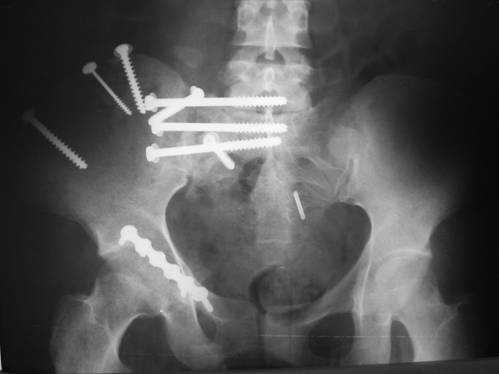

Дорогой Андрей. Мы имеем дело с комбинированной (ротационно и вертикально) нестабильностью таза со смещением правого гнемипелвиса. При таких переломах, фиксация только переднего полукольца вне зависимости от метода фиксации, как уже было сказано Djoldas Kuldjanov, M.D., не может создать адекватной фиксации. И перелом пластины был вполне ожидаемым после активизации пациента. Смещение сохраняется, и по-видимому не 2 см., а все 4, если не более. Разница всего (+2 см) по конечностям как вы указываете, скорее скомпенсировано позвоночником и протезом. Дополнительные снимки или КТ исследование помогли бы уточнить степень смещения с точностью до мм., выявить перелом поперечного отростка пятого поясничного позвонка, или помимо разрыва правого крестцово-подвздошного сочленения выявить перелом боковой массы крестца справа и т.д. При возможности, конечно, все это желательно сделать. Но мало что изменится с практической точки зрения, т.к. задача - это низведение репозиция и надежная фиксация правого гемипелвиса. Учитывая плачевный опыт стержневого аппарата, давность травмы совершенно очевидно, что поставленная задача достижима при открытой репозиции и одномоментной фиксации переднего полукольца с артродезированием правого крестцово-подвздошного сустава. Операция выполняется в положении больного на здоровом боку или полубоку из расширенного трансоссального подвздошно-пахового доступа с переходом на лонное сочленение доступом по Pfannenstiel. Указанный доступ обеспечивает подход к крестцово-подвздошному сочленению как спереди так и сзади. После артродезирования выполняется синтез лонного сочленения. Клинический пример

Пациентка С.26 лет. Травма за 6 месяцев до поступления

Укорочение правой нижней конечности до 10см

23.09.2003. Одновременный остеосинтез переднего и заднего тазовых полуколец

Результат через 10 дней

и 8месяцев после операции

> Результат через 10 дней и 8месяцев после операции

Да, забыл сказать - отличная работа, искренне восхищаюсь. Кость рубите по Judet (немного не разобрался по рисунку)?